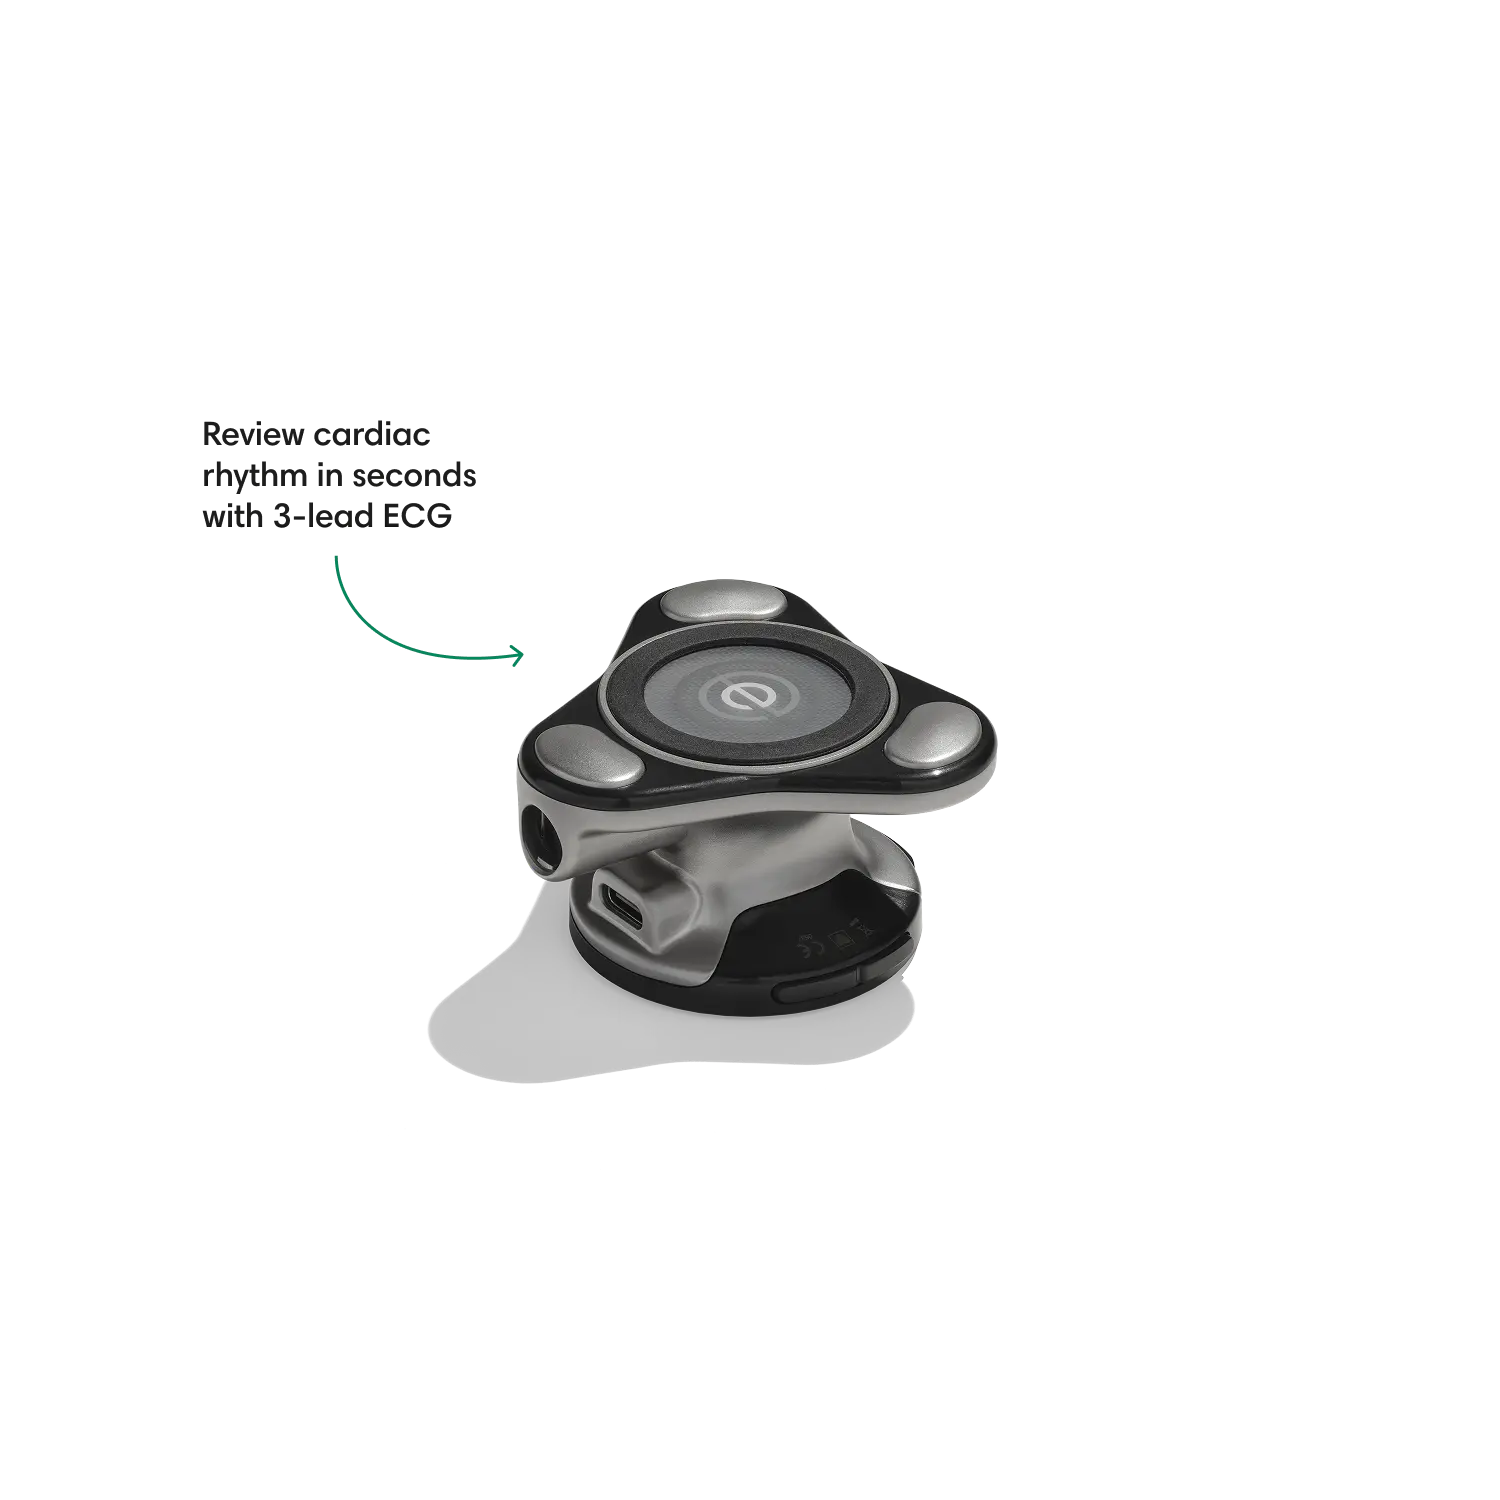

Go beyond sound alone.

For the first time ever, measure heart rate, visualize 3-lead ECG, and see detection results — right on a built-in, full-color display.